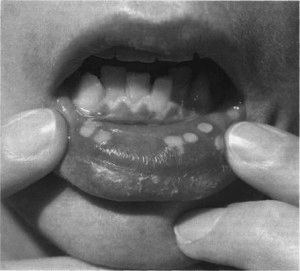

Досить поширене захворювання, що виявляється у вигляді болючих виразкових висипів в порожнині рота. При цьому слизова гіперемована, червоного кольору, острівці дрібних бульбашок вражають частково або всю порожнину рота. На тлі цих висипань підвищується температура, погіршується загальний стан хворого, з'являється хворобливість в регіональних лімфатичних вузлах, пропадає апетит, виникає ломота в тілі. У дорослих захворювання протікає в більш гострій формі, ніж, у дітей.

Метсно застосовуються мазі на основі інтерферону. Для полоскання порожнини рота використовують розчин фурациліну, хлораміну або хлоргексидину. Знеболюючі препарати на основі ледокаїн. Вірус герпесу, який безпосередньо викликає цю форму стоматиту при попаданні в організм, зберігається протягом усього життя. При ослабленні імунної системи він проявляється висипаннями. Тому з метою профілактики рекомендовано підтримувати імунні функції організму, не переохолоджуватися, остерігатися травм порожнини рота.

Кожне з описаних захворювань має в своєму анамнезі різні форми висипань у вигляді бульбашок, червоні, білі, прозорі, з нальотом або без нього, фото деяких з них докладаємо. У деяких випадках ознаки патологій можуть бути схожими, але при цьому лікування принципово різний. Для правильно складеного плану заходів спрямованих на якнайшвидше одужання слід точно встановити діагноз, а в цих цілях необхідна тільки допомога фахівця. При виникненні тих чи інших патологічних змін негайно звертайтеся за медичною допомогою, не вдаючись до самолікування.